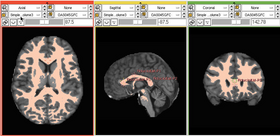

As shown in Figure Figure1, 1, the focus of our segmentation is on seeded region growing The algorithm operates by assigning the highintensity pixel coordinates as starting points of the segmentation procedure and expanding the region of interest (ROI) by checking their neighboring pixels on CT image Seeded region growing which starts from a selected seed point is one of the simple and popular segmentation methods 8, 9 It is one of the hybrid methods proposed by Adams and Bischof 1 , and the regions are grown by merging a pixel into its nearest neighboring seed region Image segmentation with region growing is simple and can be used as an initialization step for more sophisticated segmentation methods In this note, I'll describe how to implement a region growing method for 3D image volume segmentation (note the code here can be applied, without modification, to 2D images by adding an extra axis to the image) that uses a single seed